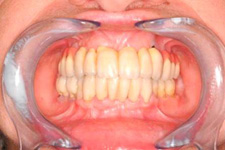

Klasickým příkladem a indikací pro použití implantátu je ztráta jednoho zubu (v tomto případě v předním – frontálním úseku) v jinak zdravém, nepoškozeném chrupu.

Nejčastější příčinou takové ztráty je sportovní nebo dopravní úraz.

Náhrada jednoho zubu pomocí implantátu je možná také v postranním úseku chrupu. Při ztrátě většího počtu zubů ve frontálním nebo postranním úseku může být mezer uzavřena větším počtem jednotlivých implantátů.

Při ošetření pomocí jednotlivých implantátů zůstávají sousední zuby neporušené – intaktní. Při klasickém ošetření pomocí můstků musejí být tyto zuby obroušeny!